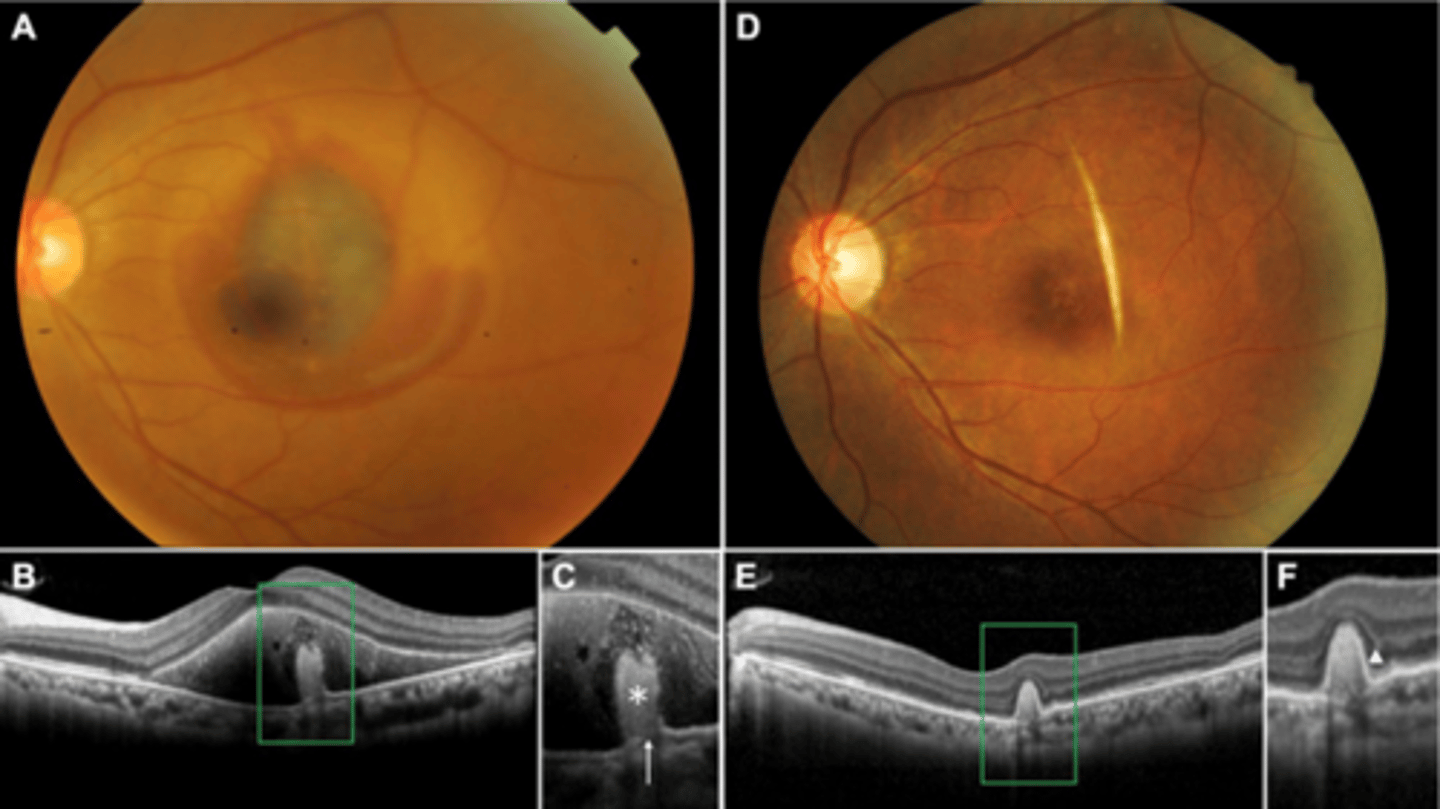

How does choroidal rupture appear on OCT here?

loss of RPE continuity at site of rupture = inner choroid atrophy

How does choroidal rupture appear on OCT here?

RPE disruption

+/- hemorrhage